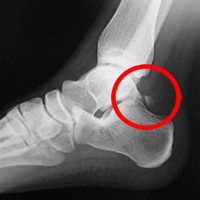

足関節の距骨という骨の後ろ側が大きく突き出していたり、離れて過剰骨となっていたりする方(三角骨といいます)が何度も足関節を底屈すると、その骨が脛骨と踵骨の間に挟まりこみ(インピンジメント)足関節の後方に炎症を起こし、痛みの原因となるのです。

単純レントゲン写真

(矢印)